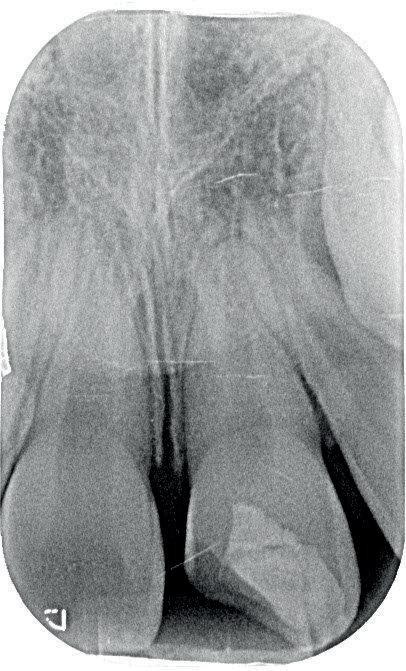

1. Helaas is er van de betreffende casus geen initiële lichtfoto gemaakt bij de spoeddienst. Dit is een foto van een vergelijkbaar trauma, met een avulsie van element 21. De overige elementen zijn gespalkt met een TTS.

2. Element 11 is op jonge leeftijd ankylotisch geworden. Het bot en de

gingiva zijn achtergebleven in groei. De incisale rand is met composiet meerdere malen verlengd (met dank aan Tristan Staas).

3. De wortel van element 11 is voor een groot deel vervangen door bot. Er is geen duidelijk PDL meer zichtbaar aan de distale zijde.

ligament onherstelbaar beschadigd is. Dit zal zorgen voor vervanginsresorptie van de radix en dus ankylose. Door de verticale groei van de schedel die er op jonge leeftijd nog plaatsvindt, zal dit op lang termijn een esthetisch probleem opleveren. Het element blijft namelijk achter in groei en het bot en dus ook de gingiva zullen niet meegroeien (foto 2). Maar wat doen we nu? Want we hebben nu wel een serieus probleem!